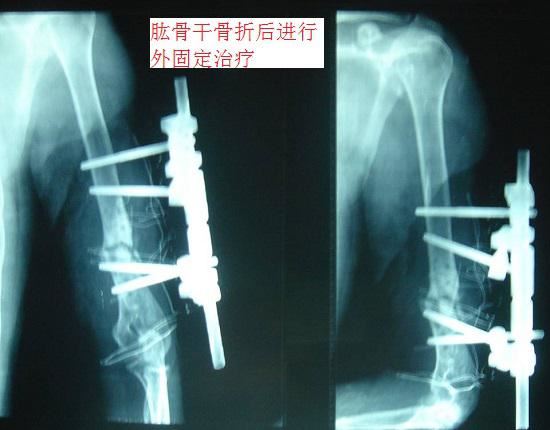

1、治疗手段。外固定是一种介于切开复位内固定(手术治疗)和保守治疗之间的骨折治疗手段,主要思路就是用克氏针等器械将移位部分复位,在骨折位置上下两端打入稳固装置(例如:钢钉)并通过体外支架连接,以实现骨折部位的固定(如下图所示)。肱骨骨折后外固定的治疗手段不需要进行大范围的软组织切开,还能够较好地保持断端对线,确保骨骼快速愈合;缺点在于外支架的保护相对复杂,需要保持良好的松紧度以确保血运和神经组织功能,;且要定期进行影像检查并调整对线。2、适应证。比较适用于开放型的、肱骨干部位的、伴有广泛软组织挫伤(或存在大范围感染)的肱骨骨折;较少用于肱骨头和肱骨近端的骨折。